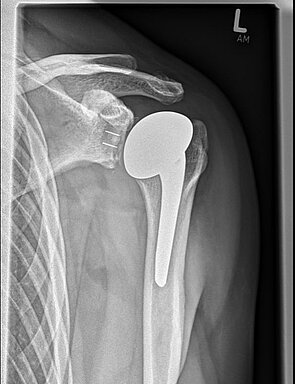

Einen weiteren Schwerpunkt in der Traumabehandlung stellt die Versorgung von Schulterbrüchen dar.

Während bei jüngeren Patienten die Rekonstruktion von Knochen und Gelenken im Vordergrund steht, führt bei älteren Patienten häufig der Gelenkersatz zur schnelleren Wiederherstellung der Beweglichkeit.

Hierfür kann die umfangreiche Erfahrung der orthopädischen Klinik in der Schulterendoprothetik angewandt werden. Dazu werden die Art der Endoprothese und die Einsatzmöglichkeit individuell geplant und umgesetzt.